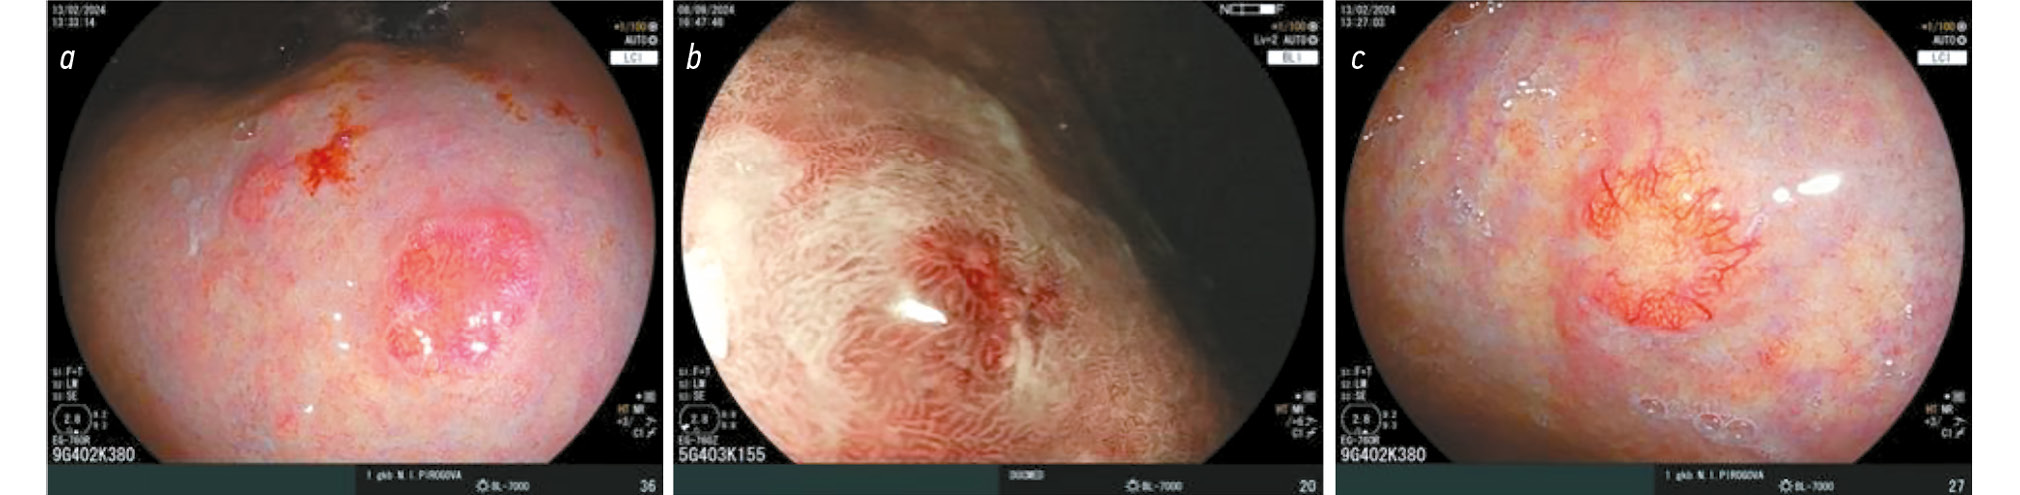

Doyama et al. described the appearance of white spherical structures and glomus-like formations when the gastric body was examined with optical magnification. White spheres, initially identified at the margin of differentiated gastric cancers, represent necrosis and apoptosis of neoplastic cells in dilated fundic glands. In autoimmune gastritis, white spheres were initially described as small whitish protrusions. However, due to the similar endoscopic appearance of these protrusions in cancer and autoimmune gastritis, both findings are now collectively referred to as white spheres (Fig. 5) [43]. The spheres are detected in 32% of cases. Iwamuro et al. examined the morphological substrate of these white spheres and demonstrated that they arise from the blockage of fundic glands by neutrophils, mucus, and necrotic parietal cells [44]. Glomus-like formations in the gastric body result from enterochromaffin-like (ECL) cell hyperplasia. These formations were first described by Drapkina et al. (Fig. 6) [45].

Fig. 5. White globe appearance on the surface of mucosa in white light (a) and in narrow-band mode (b). © Eco-Vector, 2025.

Fig. 6. Glomus-like lesions of the stomach (a), glomus-like lesions with white globe appearance and areas of foveolar hyperplasia (b). © Eco-Vector, 2025.

According to Greenson et al. [46] and Itsuno et al. [47], glomus-like structures larger than 0.5 mm are considered neoplastic changes.